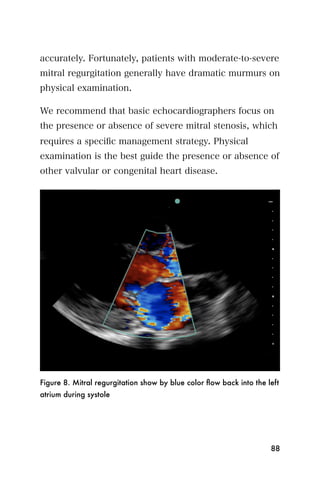

Recommended reading

1. Andrews MW. Ultrasound of the spleen. World J Surg

2000;24:183-7.

2. Bonnard P, Lanuit R, Dompnier JP, et al. [Predictive

ultrasonographic criteria for portal hypertension due to